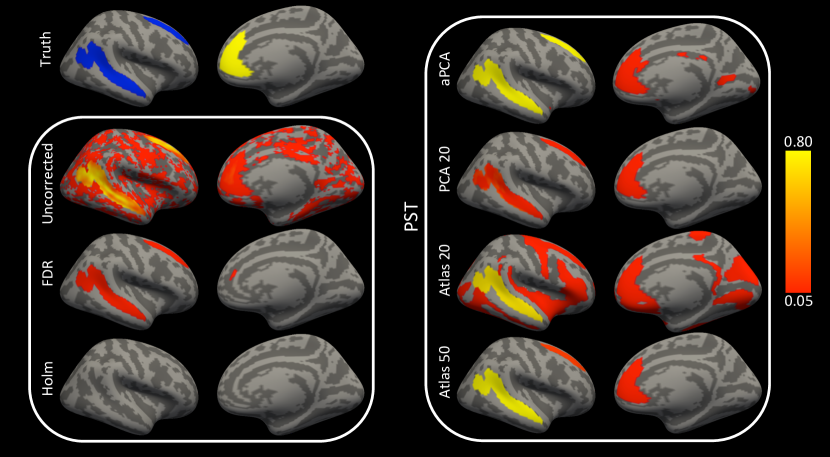

The vertexwise error rate describes how effective a procedure is at controlling the error rate for the unprojected scores at each location. The vertexwise error rate of the PST inference procedure for the unprojected scores using the PCA 10 basis is low while maintaining better vertexwise power than BH (Figure 4; PCA 10). This is because in any given sample there may be a high false positive rate, but the errors across samples do not appear in the same locations. The BH and Bonferroni corrections both work well at controlling the vertexwise type 1 error rate but have lower power compared to the PCA-based PST procedure (Figure 4). The bases constructed from the anatomical atlas tend to have large regions of vertexwise type 1 error for the unprojected scores. At the largest basis dimension the atlas allows for enough specificity to reduce the vertexwise error. All methods have lower power to detect the positive cluster than the two negative clusters. This is possibly due to the characteristics of the covariance structure in the positive cluster which overlaps gyral and sulcal regions.